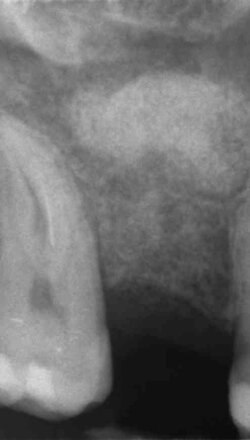

Implantologia Guidata: chirurgia mini-invasiva di alta precisione.